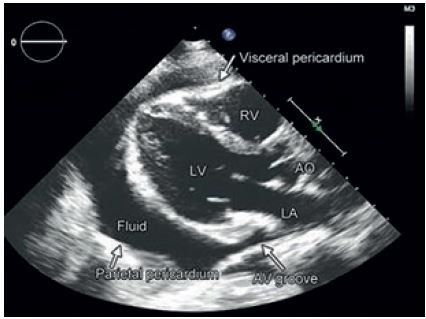

4. Echokardiografie je hlavní zobrazovací metodou v první linii diagnostiky perikarditis. Dokáže kvalitativně a kvantitativně zhodnotit rozsah perikardiální efuze měřením anechogenního prostoru mezi viscerálním a parietálním listem perikardu v enddiastole (výskyt výpotku u 60 % případů). Rozlišujeme malý perikardiální výpotek (< 10 mm), střední (10–20 mm) a velký výpotek (> 20 mm). Ve většině případů nacházíme malý výpotek (80 %), méně často střední (10 %) nebo velký výpotek (10 %), s manifestací srdeční tamponády nebo bez ní (obr. 3, 4). Typickým echokardiografickým nálezem při srdeční tamponádě je obraz „swingujícího srdce“ ve výpotku, kolaps pravostranných srdečních oddílů v diastole, abnormální pohyb komorového septa, zvýrazněná respirační variabilita průtoku mitrální a trikuspidální chlopní > 25 %. V případě myoperikarditis může být systolická funkce komor snížená. V diferenciální diagnóze ischemie myokardu hodnotíme poruchy kinetiky stěn levé komory. Důležité je sledovat dynamiku rozvoje perikardiální efuze, nejen aktuální objem. U pacientů s akutní virovou perikarditis může být echokardiografický nález normální.

Obr. 4 Echokardiografické zobrazení perikarditis s rozsáhlým výpotkem – parasternální pohled. CT hrudníku dokáže zobrazit nejen struktury srdce a perikardu, ale také může odhalit záněty a tumory plic, lymfadenopatii mediastina, metastatický rozsev plic a pleury, aortální disekci nebo aneurysma.